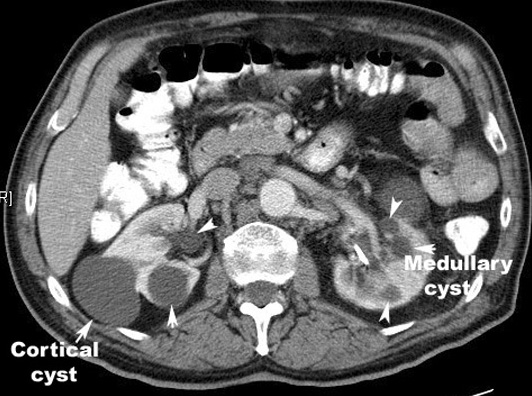

Contrast CT characteristics: